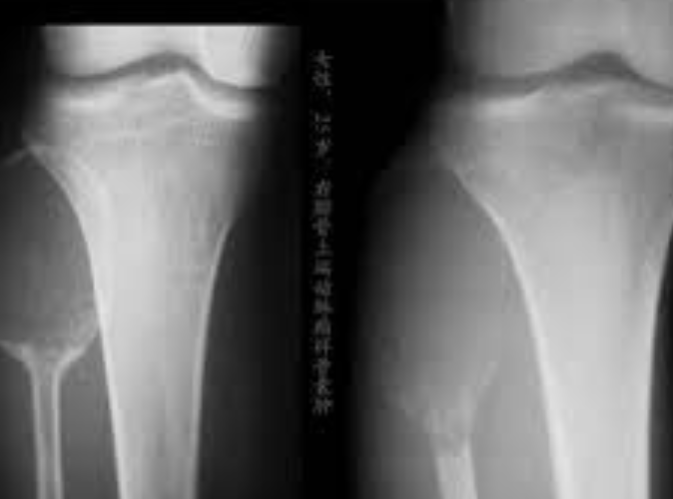

骨肉瘤和尤文氏肉瘤是两种主要的儿童骨肉瘤类型。它们的特征是骨骼细胞异常生长,最常见于儿童和青少年。了解这些癌症的性质对于有效治疗至关重要。因此早期诊断对改善儿童骨癌的预后具有重要意义。识别骨痛、肿胀和不明原因骨折等体征和症状对于及时干预至关重要。